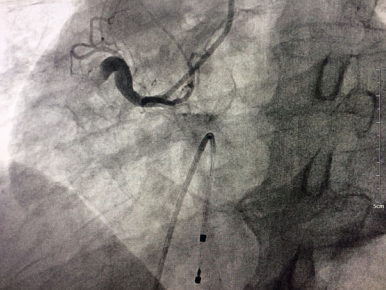

术前右冠动脉近段完全闭塞

手术台上,老人心率进行性下降到40次/分左右,病情极其危重。心内科介入手术团队迅速为患者植入心脏临时起搏器,在临时起搏器的保护下,医生从血管穿刺开始仅耗时15分钟就完成了冠脉造影术,但检查结果十分不乐观:右冠状动脉自近端完全闭塞,可见血栓影,袁小蓉立即采用特殊的药物替罗非班注射液10ml在冠脉内推注。在数分钟内,医生迅速、准确的为将导丝通过闭塞段,采用血栓抽吸导管进行血栓抽吸,植入支架,打通右冠状动脉血管,手术成功了!